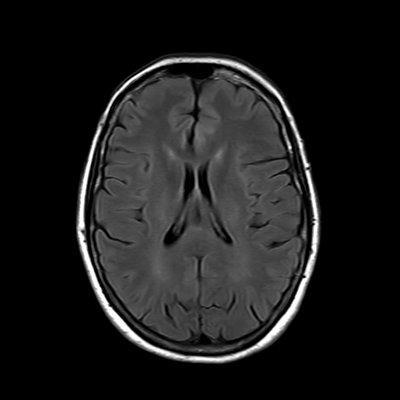

You also obtain an MRI of his brain once it's clinically safe to do so.

MRI brain (FLAIR)